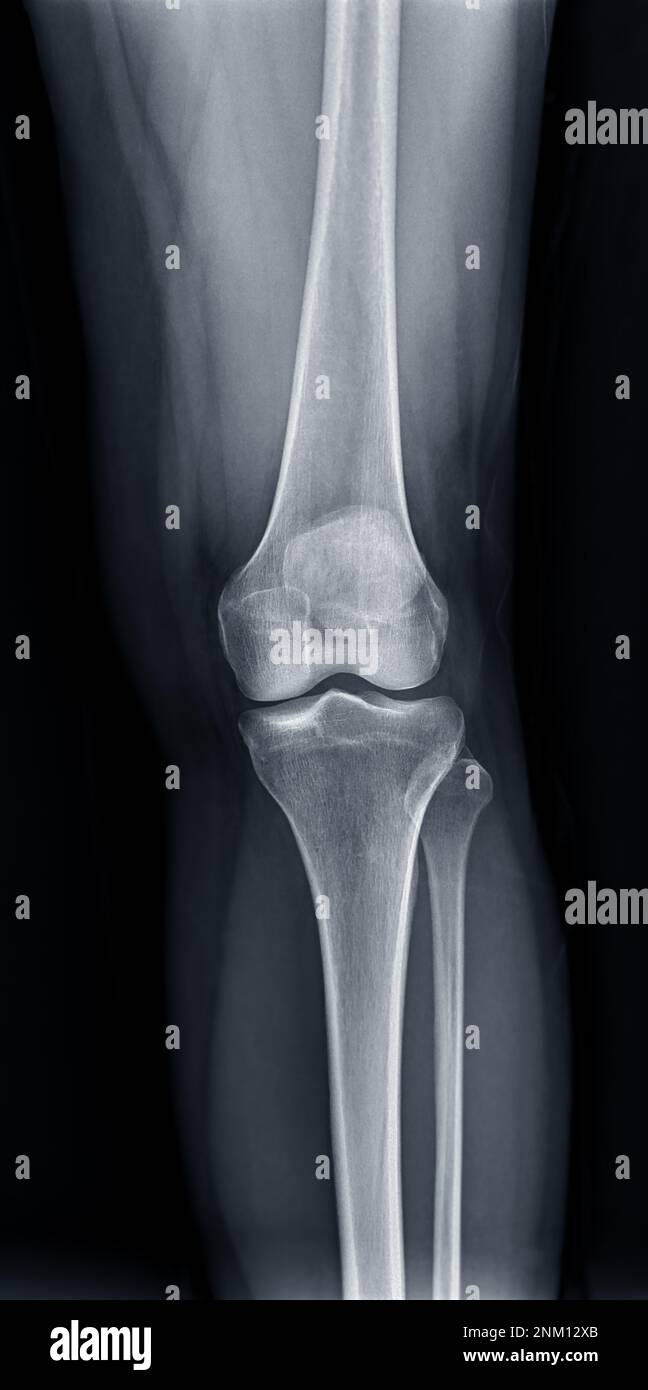

Knee X Ray With Labels . The knee series is a set of radiographs taken to investigate knee joint pathology, often in the context of trauma. The knee anteroposterior view is a standard projection to assess the knee joint, distal femur, proximal tibia and fibula and the patella. The knee radiograph approach article on radiopaedia.org provides a comprehensive guide to assessing the knee joint, including standard. Standard radiography of the lower limb. Horizontal ray (lateromedial) = supine + knee extended. It usually comprises an ap and lateral projection, although.

The knee anteroposterior view is a standard projection to assess the knee joint, distal femur, proximal tibia and fibula and the patella. The knee series is a set of radiographs taken to investigate knee joint pathology, often in the context of trauma. Horizontal ray (lateromedial) = supine + knee extended. The knee radiograph approach article on radiopaedia.org provides a comprehensive guide to assessing the knee joint, including standard. Standard radiography of the lower limb. It usually comprises an ap and lateral projection, although.